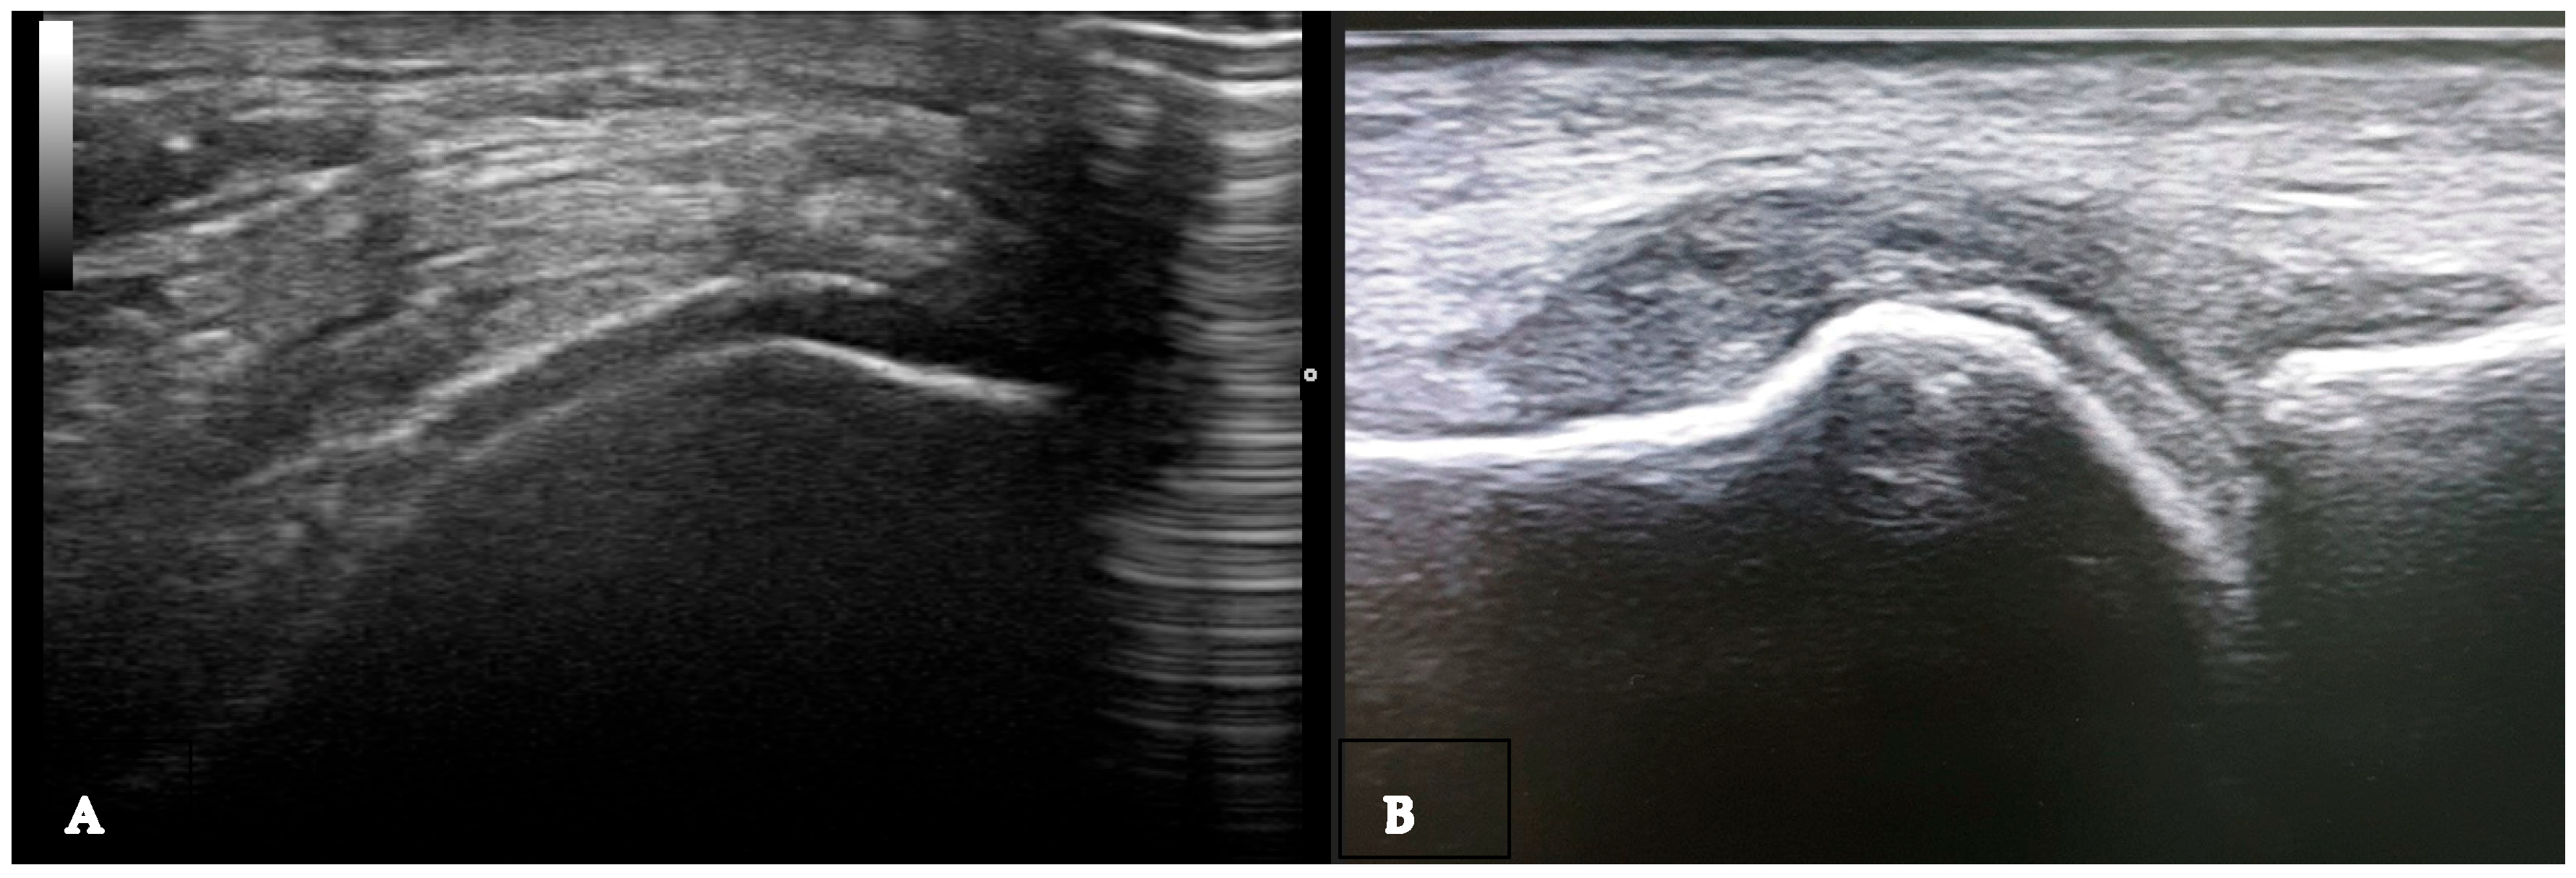

Non-specific signs. Gout is an inflammatory disease that manifests through episodes of acute arthritis. During the progression of the disease, urate arthropathy may occur, accompanied by joint damage. Similar to rheumatoid arthritis and other erosive rheumatism, joint effusion, synovial hypertrophy, and non-specific bone erosions can be found. Joint effusion can be found in gout (Table 1), and the presence of hyperechoic spots (snowstorm sign) in the synovial fluid suggests a crystalline pathology but is not specific to gout (Figure 1) [13]. Synovitis, including Doppler activity, is not considered an elementary lesion for gout because it is not specific enough to define the condition. Synovial hypertrophy and hypervascularization are not specific to gout, but their association with hyperechoic spots (bright focal areas) in the synovium strongly suggests gout. When assessing synovitis and tenosynovitis in gout patients, the definitions validated by OMERACT ultrasound group for rheumatoid arthritis are used. Synovial hypertrophy is another non-specific sign that can be found in gout (Table 1). Tenosynovitis is defined as hypoechoic or anechoic thickened tissue within the tendon sheath, with or without fluid, seen in two perpendicular planes and potentially exhibiting a Doppler signal [11,12,13].

Figure 1.

Baker cyst in transverse (A) and longitudinal (B) view with the presence of multiple hyperechoic spots “snowstorm sign”.